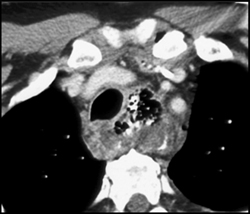

Hemopericardium